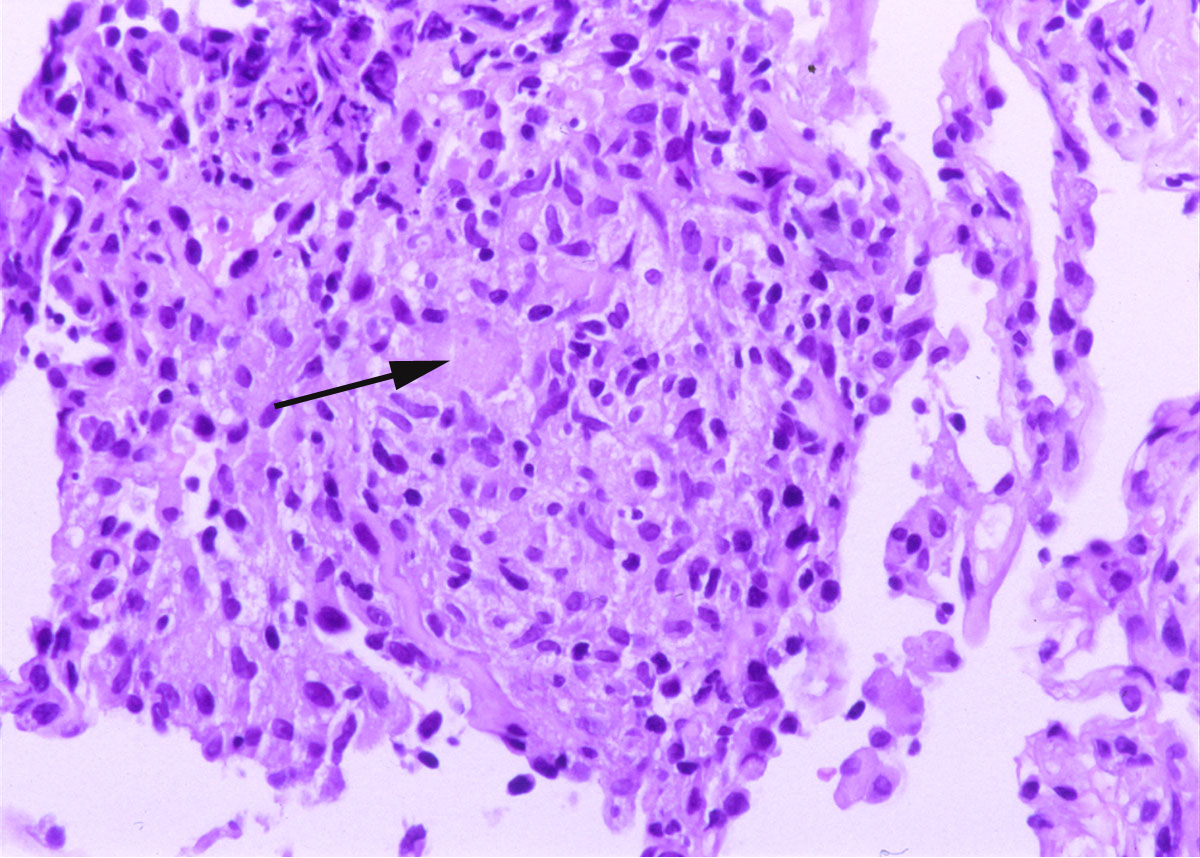

Her clinical and radiologic picture did not improve even after the two canaries were removed from her home. A subsequent bronchoscopy with bronchoalveolar lavage and transbronchial biopsy was done. The lavage revealed 75% lymphocytes and an unrevealing gram stain, GMS and acid fast bacillus (AFB) stain. Two weeks after the bronchoscopy, the lavage grew Mycobacterium avium complex (MAC). The transbronchial biopsy of the right upper lobe is shown in figure 2.

Figure 2: Lung, right upper lobe (H&E, 10 X and 40 X original magnification in Figures 2a and 2b respectively). The transbronchial biopsy of the right upper lobe showed several non-caseating granulomas (white arrows in Figure 2a) with multinucleated giant cells (black arrow in Figure 2b). No acid fast bacilli or fungal organism were identified on AFB and GMS stains respectively.